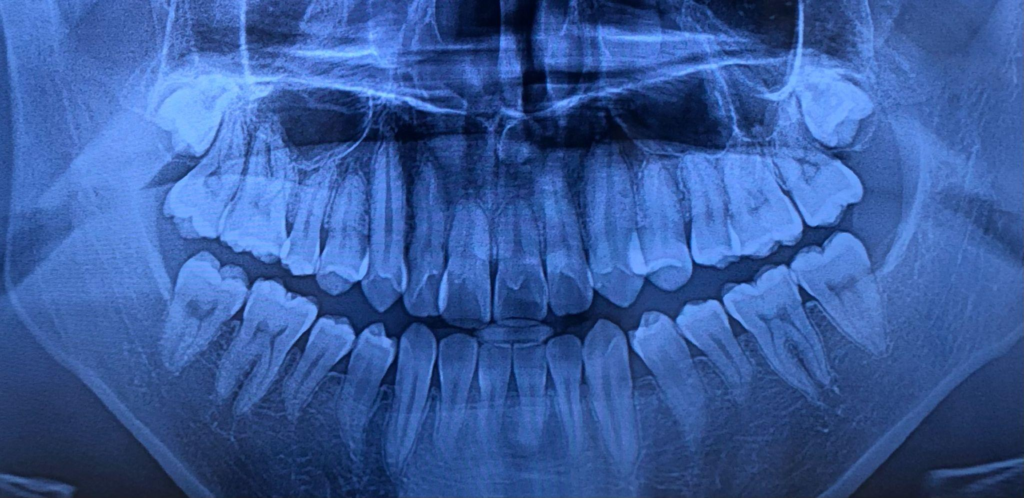

私は生まれつき下の親知らずが2本とも存在せず、上の親知らずも今のところ頭すら出てきていません。かなりラッキーなケースだと思いますが、これもレントゲンを撮ってもらわなければ一生気づかなかったはずのことです。

親知らずが「あるのか・ないのか」「どんな向きで存在しているのか」を自分の目だけで判断することはほぼ不可能です。だからこそ、痛くなる前に一度チェックしておくことが大切だと感じています。

ひとつでも当てはまる場合は、一度レントゲンやCTで詳しく確認しておくと安心です。

親知らずの位置や向きをCTで立体的に確認